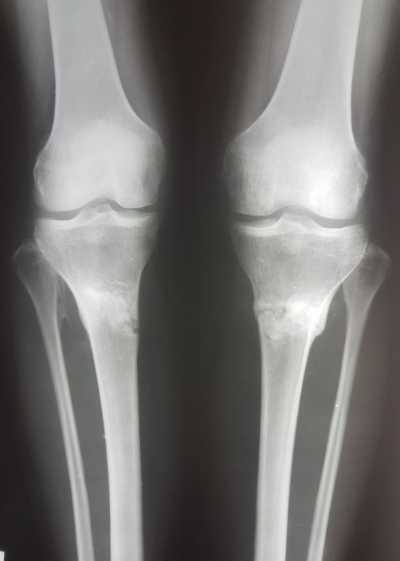

Рентген снимки через 1,5 месяца с момента снятия аппаратов